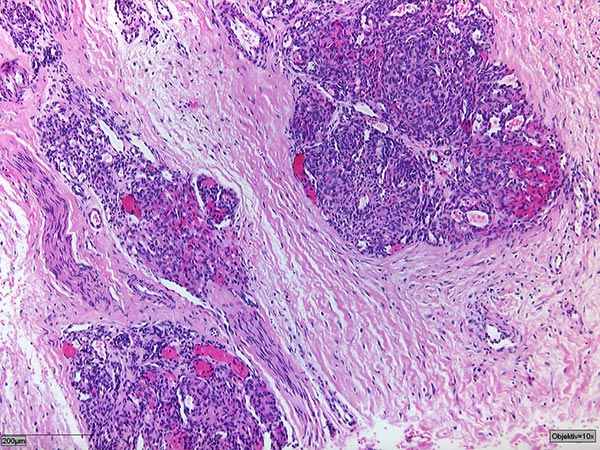

Histologie in Hämatoxilin-Eosin-Färbung.

Der Tumor besteht aus irregulären, glomeruloiden Gefäßknoten die das Weichgewebe diffus infiltrieren („cannon-ball“) und mit einer Stromadesmoplasie einhergehen.